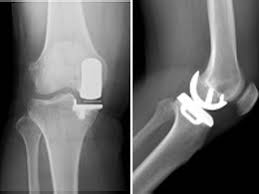

무릎 인공관절 수술, 왜 필요한가요?

무릎관절은 체중을 가장 많이 지탱하는 관절입니다. 나이가 들수록 연골은 점차 마모되고, 충격을 흡수하는 능력도 감소합니다. 이로 인해 통증, 뻣뻣함, 운동 제한이 생기며, 이런 증상이 악화되면 인공관절 수술이 필요해집니다.

퇴행성 관절염 외에도 류마티스 관절염이나 외상 후 관절 손상이 심각할 경우 수술이 권유되며, 수술을 통해 환자는 통증 없이 보행이 가능해지고 일상생활로 복귀할 수 있게 됩니다.